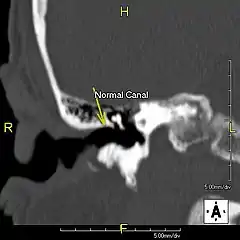

Conduit auditif normal Conduit auditif normal